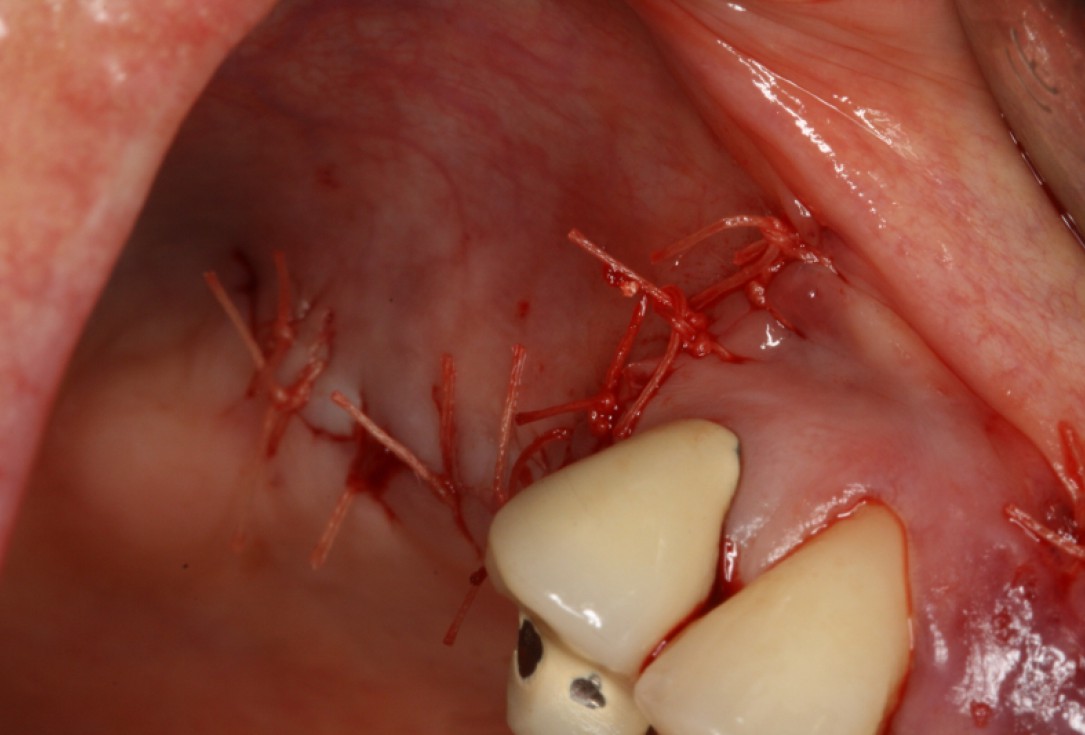

06/20 - Tension-free wound closureGBR with maxresorb® & Jason® membrane - Prof. Dr. Dr. D. Rothamel